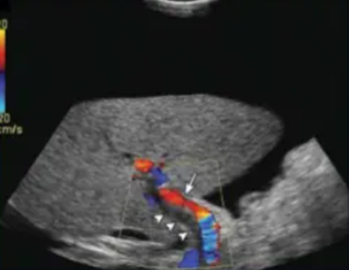

portal vein thrombosis (PVT)